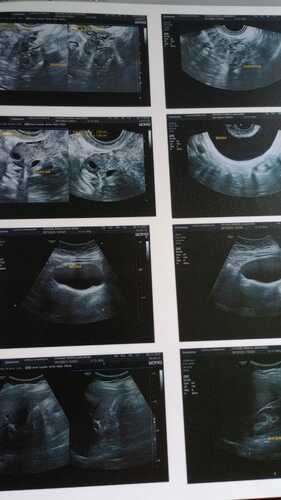

Foi aí que diagnosticaram que eu tenho endometriose profunda, faço uso de medicação contínua, o Allurene que é um medicamento que contém hormônio (dienogeste) para o tratamento dos sintomas dolorosos das lesões da endometriose (migração e crescimento do tecido da parede interna do útero fora da cavidade uterina), o qual não é fornecido pela farmácia do SUS por ser de alto custo e preciso comprar mensalmente. Sem essa medicação sofro de fortes hemorragias, barriga fica muito inchada, tenho fortes cólicas e muitas vezes preciso ser internada pra tomar medicação e suportar a dor.

Já tentei 03 vezes o pedido da realização da cirurgia, que foi negada pelo SUS. Então, juntei recursos e fui consultar com um especialista particular, Dr Igor Chiminácio, na cidade de Pato Branco-PR. Este médico afirmou ser possível a realização da cirurgia, será muito delicada, pois é preciso ser retirado o meu útero, os dois ovários, apêndice, parte do meu umbigo e descolar o mesmo do intestino, pois esta todo aderido, inclusive o meu nervo ciático esta prejudicado em decorrência dessas aderências. Estou aguardando a autorização de uma ressonância pra saber se será necessário a retirada de parte do intestino.